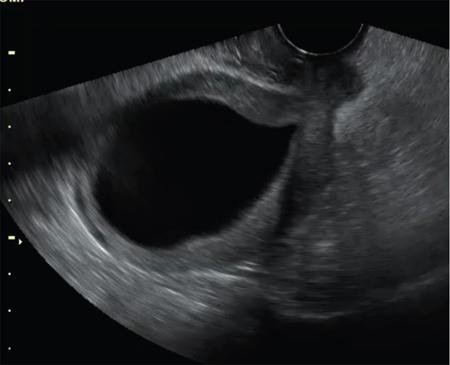

John De Lindsay, Usha Nandini Ganeshan, Vidya CERVICITIS Acute or chronic inflammation of cervix is termed as cervicitis. Noninfectious causes of cervicitis include trauma, pelvic radiation and chemical irritation. Most acute cervicitis is secondary to an infectious agent, commonly Trichomonas vaginalis, Candida albicans, herpes simplex virus, Neisseria gonorrhoeae and Chlamydia trachomatis. Patients usually present with purulent or mucopurulent cervical and vaginal discharge and may complain of pelvic pressure or discomfort. The cervix in patients with acute cervicitis shows a diffusely heterogeneous echotexture of the cervical mucosa and stroma, but the key finding is markedly increased vascularity on colour Doppler. Absence of mass is the differentiating feature between inflammation and malignancy. Free fluid can also be seen in the pouch of Douglas. CT may demonstrate an enlarged uterine cervix, an abnormally enhancing endocervical canal, and parametrial fat stranding. Retention cysts of the uterine cervix are termed as nabothian cysts. They are formed as a result of the healing process of chronic cervicitis. They are usually less than 1 cm, incidentally detected at imaging and are considered a normal finding in multiparous women. They may enlarge and become symptomatic because of mass effect, but this happens infrequently Majority of nabothian cysts, appear as small, simple anechoic cysts in the cervix, with no internal vascularity (Fig. 11.18.1.1). Their appearances can also vary depending upon any internal proteinaceous or haemorrhagic content, cyst clustering and deeper cervical stromal extension. US features that raise concern for malignancy include a solid component and marked vascular flow in the lesion at colour Doppler US. Tunnel cluster is a special variant of nabothian cyst with complex multicystic dilatation of the endocervical glands. Though macroscopically it resembles adenoma malignum, the epithelial cells of the tunnel cluster, do not show any cellular atypia similar to nabothian cyst. Nabothian cysts exhibit intermediate or slightly high signal intensity on T1-weighted (T1W) images and have prominent high signal intensity on T2-weighted (T2W) images. Presence of a solid component surrounding or separating the cysts gives us a clue to differentiate adenoma malignum from a benign nabothian cyst cluster. MR imaging also may be helpful in distinguishing adenoma malignum from benign multicystic lesions of the cervix. MR imaging features associated with malignancy include irregular margins, enhancing solid components, local invasion and metastases. CERVICAL STENOSIS Stenosis of the uterine cervix is the pathological narrowing of the cervix. The term cervical stenosis is clinically defined as cervical narrowing that prevents the insertion of a 2.5-mm-wide dilator. In utero exposure to diethylstilbestrol contributes about 20% of the cases. Often associated with endometriosis. Cervical stenosis in menopausal patient is asymptomatic. Retrograde menses may occur in women of reproductive age, thus posing a risk of endometriosis. Dysmenorrhea is present in up to 50% of patients with cervical stenosis. If the stenosis is severe enough, it may result in proximal obstruction resulting in haematometra, hydrometra, pyometra, haematosalpinges. The symptoms depend upon the severity of stenosis. Other potential consequences include infertility, impediment to assisted fertility techniques – embryo transfer and intrauterine insemination. Any pathological process that can cause inflammation of the cervical mucosa, resulting in erosion and regeneration can result in cervical stenosis. This includes: Narrowing of the endocervical canal may be observed (normal diameter: 0.5–3.0 cm). Complete obliteration of the cervical os will prevent insertion of the hysterosalpingographic catheter. The endocervix can be normal in appearance or slightly thickened. If post irradiation, the cervix may demonstrate loss of the normal zonal architecture. There may be mild to moderate fluid distension of the endometrial cavity (Fig. 11.18.2.1). If the fluid has internal echoes a careful search for potentially associated endometrial or cervical mass lesions, should be done. Complex, particulate intracavitatory fluid with its heterogeneous echogenicity at ultrasound may mimic a solid lesion; however, the absence of detectable flow at colour Doppler US and the central location should suggest the correct diagnosis. May reveal complications due to cervical stenosis such as hydrometra and haematometra and haematosalpinges. Though the cervix may be appear normal, the uterine cavity may be fluid filled. Auxiliary findings may suggest an underlying cause, such as an obstructive mass lesion, or post radiation bowel wall thickening. In equivocal cases, MR imaging may be useful to differentiate complex endocervical fluid from a mass. In selected situations, gradual dilatation of the cervix under ultrasound guidance, can be an effective treatment. Depending on severity of disease, other treatment options include insertion of laminaria tent, hysteroscopic cervical excision or in extreme cases total hysterectomy. CERVICAL POLYPS The common cervical polyps are prolapsing endometrial polyps. They are seen in endocervial canal. Endometrial polyps are common and a frequent cause of abnormal uterine bleeding. They account for approximately 30% of cases of postmenopausal bleeding. In menstruating females, they may cause intermenstrual bleeding, metrorrhagia, and infertility. Polyps can be histologically characterized as localized hyperplastic overgrowths of glands and stroma covered by epithelium. The typical appearance of an endometrial polyp at sonography is a well-defined, homogeneous, polypoid lesion that is isoechoic to hyperechoic to the endometrium with preservation of the endomyometrial interface (Fig. 11.18.3.1). There usually is a well-defined vascular pedicle within the stalk demonstrated on colour Doppler sonography (Fig. 11.18.3.2). Uncommon features of polyps include multiplicity, cystic components, a broad base and hypoechogenicity or heterogeneity. Occasionally, polyps can have a heterogeneous echotexture with multiple cysts. This complex appearance may be due to haemorrhage, infarction or inflammation within the polyp. Sonohysterography is an ultrasound technique in which the endometrial cavity is distended with saline allows evaluation of single layer of the endometrial lining and enables us to reliably distinguish focal from diffuse endometrial pathologic conditions. Focal lesions are defined as lesions occupying less than 25% of the endometrial surface area and diffuse lesions involve a larger percentage of the endometrial surface area. Saline infusion sonohysterography which involves the infusion of fluid to visualize the endometrium is a simple, well-tolerated and inexpensive procedure. Sonohysterography is best performed as soon as possible after the bleeding cycle has ended when the endometrium is thin. When the patient has irregular bleeding, that she cannot tell what is actual menses, in such cases it may be helpful to use an empiric course of a progestogen such as medroxyprogesterone acetate 10 mg daily for 10 days as a medical curettage and then time the ultrasound examination to the withdrawal bleed. The decision about whether to obtain cultures and use of antibiotics depends very much on the patient population with which the physician deals with. Anaesthesia or analgesia is not required. A bimanual examination to know the version of the uterus is done. The vaginal speculum is inserted. Under sterile aseptic precautions, a catheter is inserted into the cervix. This is done by grasping the cervix with a ring forceps feeding it through the os. A cervical stabilizer may be used and it will be less painful, less traumatic and does not cause bleeding from the cervix. The speculum is removed without dislodging the catheter. The vaginal probe is then reinserted. A 10-mL syringe is attached to catheter. Scanning in long-axis projection, fluid is instilled while watching the video monitor. In that long-axis projection the transducer is removed from side to side (i.e. from cornua to cornua). The amount of fluid instilled is variable and depends on the image which is producing on the ultrasound screen. When the uterus has been completely rotated 90 degrees into a coronal plane further fluid is instilled, while fanning down toward the endocervical canal and up toward the uterine fundus. Very minimal fluid acts as a sufficient interface to distinguish anterior and posterior endometrial surfaces and outline endometrial pathology. The risk of malignant cell dissemination exists but is small. The saline infusion sonohysterography can reliably distinguish dysfunctional abnormal bleeding (no anatomic abnormality) from those with globally thickened endometrium. Endometrial polyp appears as homogeneous, well-circumscribed, polypoid lesion that is isoechoic to the endometrium with preservation of endometrial–myometrial interface. Other features can be cystic components, multiplicity, a broad base, and hypoechogenicity or heterogeneity. Submucosal leiomyomas are usually broad-based, hypoechoic, well-defined, solid masses with shadowing and an overlying layer of echogenic endometrium that distorts the endometrial–myometrial interface. They are pedunculated or have a multilobulated surface. The major advantage of sonohysterography is the accuracy in depicting the percentage of the fibroid that projects into the endometrial cavity. In contrast to the transvaginal US demonstration of polyps, which may distort measurements of endometrial thickness if made before saline infusion, at sonohysterography the uninvolved single-layer endometrium appears normal in thickness and should be measured separately from the polyp. The findings at sonohysterography determine whether a blind biopsy, hysteroscopically guided biopsy, or hysteroscopically guided dilation and curettage is the appropriate diagnostic. On MRI polyps appear T2 isointense to hypointense and demonstrate postcontrast enhancement (Fig. 11.18.3.3). Polyps generally enhance less than the surrounding endometrium but more than myometrium. Most of endometrial polyps can be reliably differentiated from submucosal leiomyomas on MR imaging with leiomyomas having hypointense signal on T2W and visualizing origin from the myometrium. A small percentage of endometrial polyps may contain malignant foci or foci of endometrial hyperplasia. Hormones (endogenous or exogenous), tamoxifen usage, nulliparity, obesity, hypertension and diabetes. Histologic patterns of endometrial hyperplasia vary from hyperplasia without atypia, which has little or no malignant potential, to severe atypia in which 20% of cases progress to endometrial cancer. Endometrial hyperplasia accounts for approximately 4%–8% of cases of postmenopausal bleeding. In sonohysterography, endometrial hyperplasia appears as a diffuse thickening of echogenic endometrial stripe without focal abnormality, uncommonly focal endometrial hyperplasia can be seen. In sonohysterography the latter form of hyperplasia is more difficult to differentiate from endometrial polyps because characteristics of the focal endometrial thickening in both conditions overlap. Endometrial cancer is typically a diffuse process, but early cases can appear as a polypoid mass. Imaging features of endometrial hyperplasia include irregular thickening of the endometrium with T2 hyperintensity compared to normal myometrium and T1 hypointensity relative to myometrium on early contrast-enhanced images. Endometrial thickening measuring >5 mm in postmenopausal females with bleeding, regardless of hormonal therapy should undergo further investigation including tissue sampling to exclude endometrial cancer. Cervical polyps are the commonest causes of intermenstrual vaginal bleeding. Most patients are perimenopausal present with symptoms including menorrhagia, postmenopausal bleeding, contact bleeding and vaginal discharge. Pathologic conditions of cervical polypoid lesions include endometrial or endocervical tissue with metaplasia, leiomyoma, inflammation or malignancy or even blood clot. Most common are endocervical polyp, account for more than 60% of cervical polypoid lesions. More commonly polyps are pedunculated, with a slender pedicle of varying length, but few are sessile. The diagnosis is made primarily with hysteroscopy. Endocervical polyps are usually seen as masses with or without cysts filling endocervical or vaginal canal. Identifying the stalk attaching to the cervical wall may differentiate it from endometrial polyp. On USG it appears hypoechoic or echogenic with a stalk. CERVICAL CARCINOMA Cervical carcinoma is the third most common gynaecological malignancy after endometrial and ovarian malignancies. It affects middle-aged females from 35 to 50 years with an average age of onset at around 45 years. It is one of the leading causes of deaths among women in developing countries. Prognosis depends on tumour size, nodal status, histological grading and staging at the time of diagnosis. So accurate staging of the disease is very important to decide the treatment strategy.